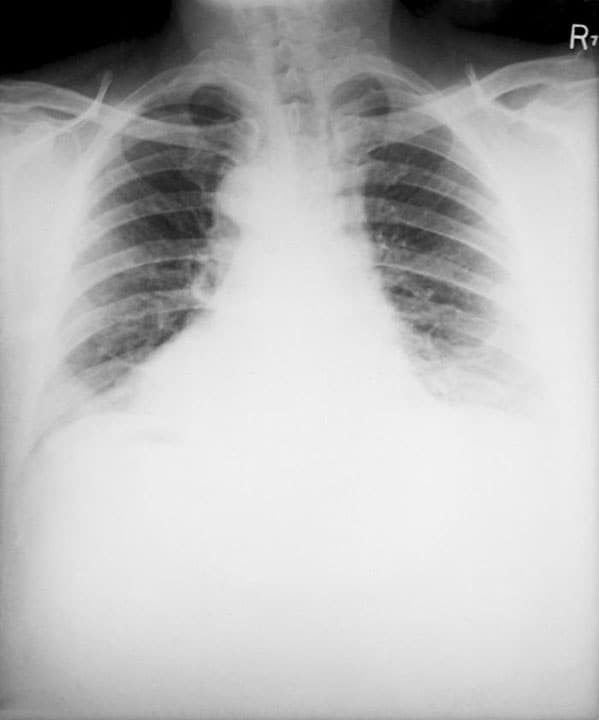

If inhalation anthrax is suspected, chest X-rays or CT scans can assist with diagnosis if the patient has commonly associated signs including mediastinal widening or pleural effusion.